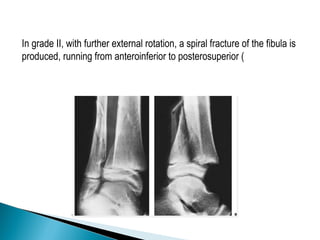

In grade II, with further external rotation, a spiral fracture of the fibula is

produced, running from anteroinferior to posterosuperior (